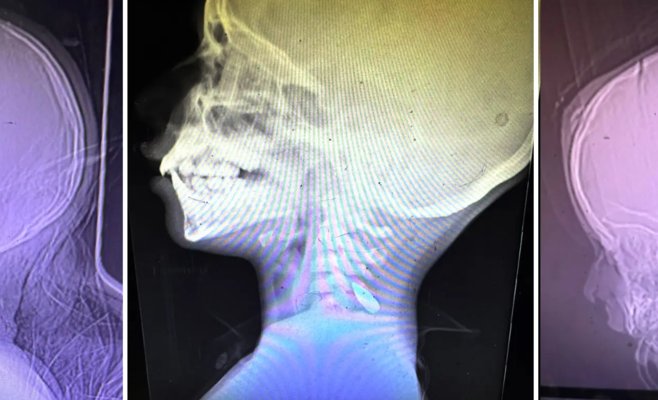

9 октября The New York Times опубликовал статью 65 американских врачей, медсестер и медицинских работников, рассказывающих о страшных последствиях войны в Газе. Особое внимание в ней уделено многочисленным случаям ранений у детей, пострадавших от одного выстрела в голову, шею или грудь. Врачи обвиняют в этом израильских военных. Однако рентгеновские снимки, сопровождавшие статью, вызвали критику и сомнения у ряда экспертов.

Автор материала, Ферозе Сидхва, приложил к статье три рентгеновских снимка, предоставленных 44-летней врачом Мими Саид из Олимпии, штат Вашингтон. Снимки показывают детей, которые, как утверждается, погибли с пулей в голове. В статье говорится, что 44 врача и медсестры сталкивались с подобными случаями, девять не видели таких пациентов, а 12 вообще не лечили детей.

Эти снимки вызвали множество вопросов среди специалистов, которые активно обсуждали их в социальных сетях.

Новостной портал Novinky проконсультировался с врачом, работавшим на зарубежных миссиях, который предпочел остаться анонимным. «Средний снимок выглядит правдоподобно, но два других вызывают сомнения, как будто они были подправлены», — отметил он. «На рентгене пуля обычно не выделяется настолько ярко по сравнению с другими объектами, и её контуры не должны быть такими чёткими. Это больше похоже на то, что мы видим на среднем снимке».

Он также отметил, что на одном из снимков не видно явного входного отверстия пули, что может быть связано с качеством рентгеновского изображения. Два других снимка не дают точной информации о местонахождении пули, что делает их непригодными для точного медицинского анализа. Возникает вопрос, почему не были представлены более информативные снимки, которые могли бы прояснить обстоятельства смерти.

Хотя сами снимки Саид не связаны напрямую с этими случаями, они подрывают достоверность подобных заявлений. В рентгеновских снимках видно, что речь идёт о пулях калибра 5,56 мм, которые используются израильской армией. Однако многие эксперты подчеркивают, что если пуля действительно была выпущена из оружия калибра 5,56 мм, она должна была пройти сквозь череп ребёнка, оставив значительные повреждения, чего на представленных снимках не наблюдается.

Бывший военный медик Ибен Фартин, участвовавший в операциях США, заявил, что пуля калибра 5,56 мм обладает огромной энергией и должна была бы нанести намного более серьёзные ранения, если бы была намеренно выпущена в голову ребёнка. Он подчеркнул, что представленные снимки не подтверждают это, а некоторые из них выглядят так, будто их просто «подправили».

Мэтт Тардио, бывший солдат «Зелёных беретов», также отметил, что пуля калибра 5,56 мм, выпущенная из карабина М4, имеет скорость, превышающую скорость звука. По его словам, она с лёгкостью могла бы пробить череп ребёнка насквозь.